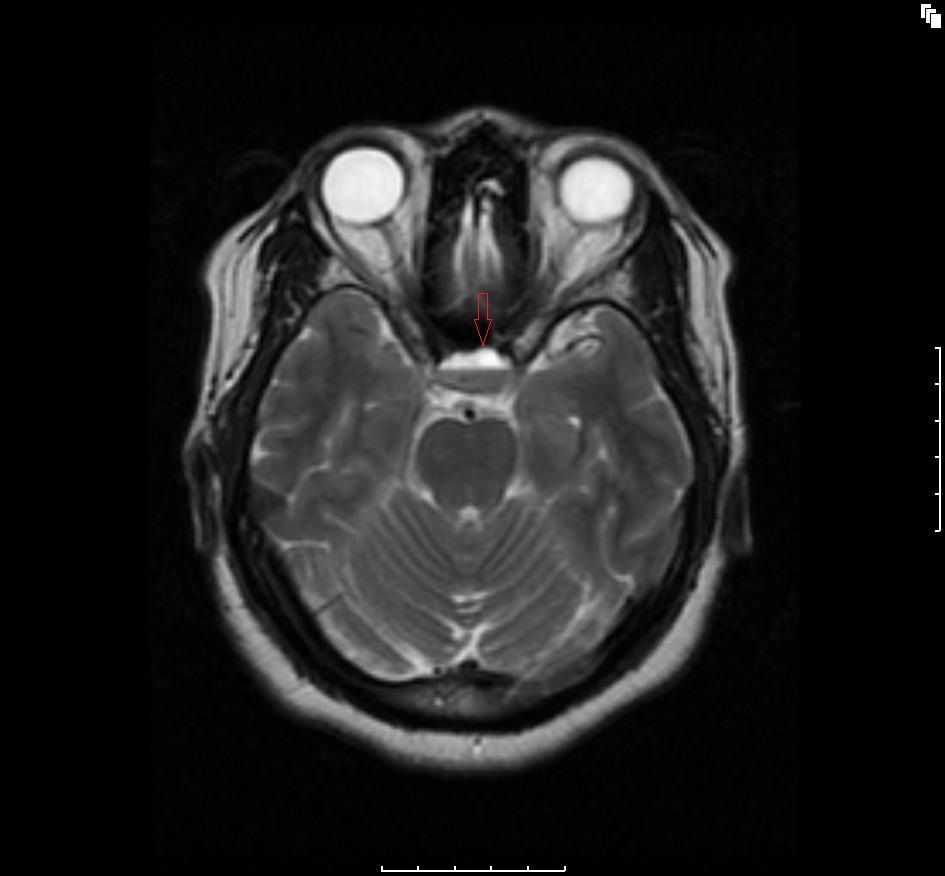

Figure A2: Axial T2-weighted image showing a fluid-fluid level consisting of a hypointense bottom layer and a hyperintense upper layer (red arrow) depicting a hemorrhagic fluid debris level.

The initial brain scans were obtained 6 months after her initial diagnosis (3 months into her pregnancy) and revealed a hemorrhagic pituitary macroadenoma (Figures A1-4). The patient recollects that a week before the scan, she suffered an episode of severe headache with visual disturbance of the right eye. She did not seek medical attention at the time but did keep an appointment for the brain imaging the following week. At the time of the imaging, she reported that her symptoms had fully resolved.